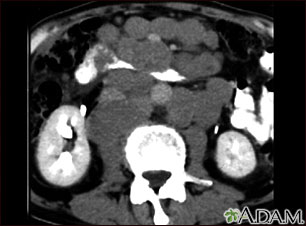

- CT scans of the chest, abdomen, and pelvis